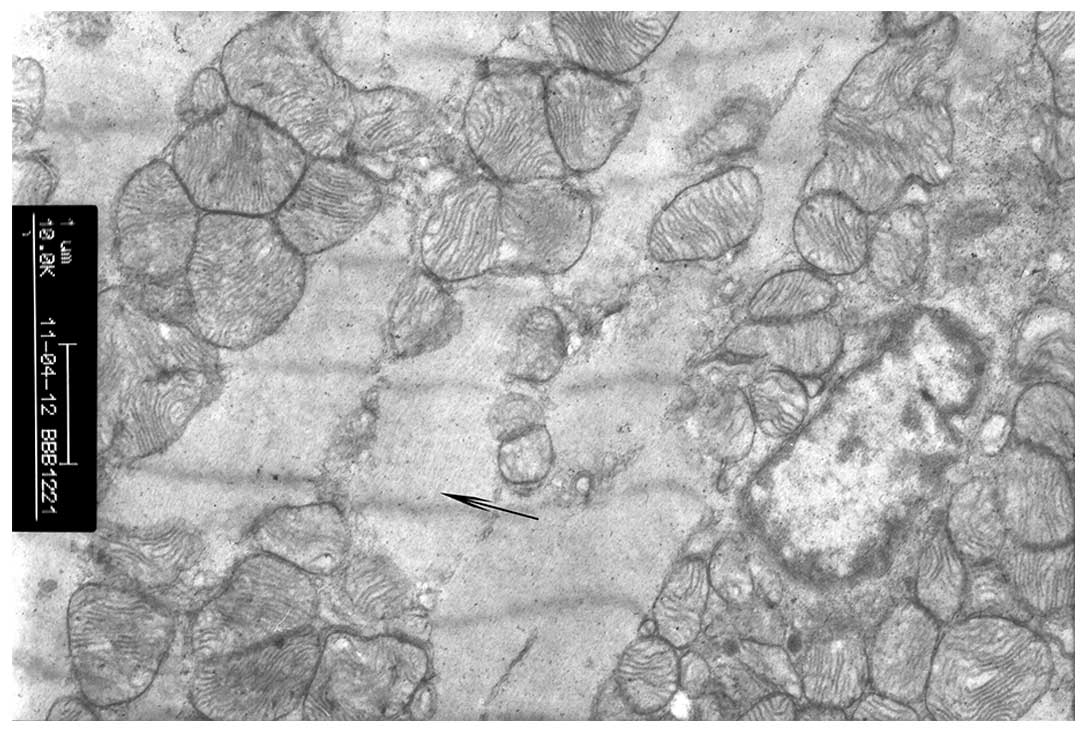

In the sham operation group, myocardial cells exhibited normal nucleus and nucleolus regions, cardiac myofibrils were arranged in neat rows, sarcomeres were clear and the mitochondrial membrane was intact (Fig. 1).

Figure 1

Rat myocardial cells in the sham operation group (magnification, ×10,000). Rats in the sham operation group were treated with intraperitoneal injection of normal saline. Myocardial cells exhibit normal nucleus and nucleolus regions, neat cardiac myofibrils, clear sarcomeres and intact mitochondrial membranes. The arrow depicts the myoneme by TEM. TEM, transmission electron microscopy.